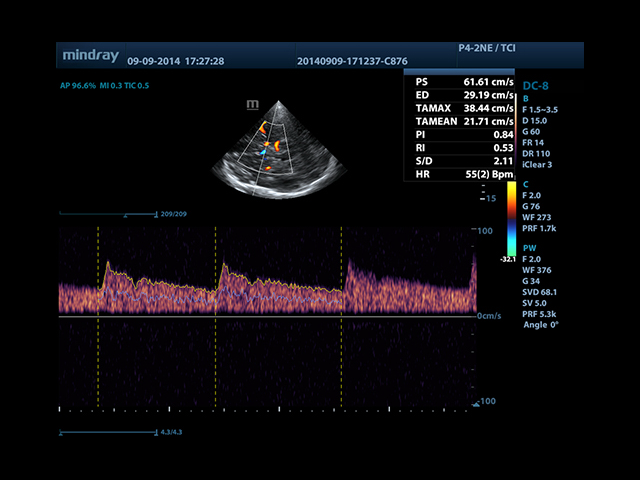

• Автоматическая трассировка допплеровского спектра с расчетом параметров и индексов

• Smart Doppler™ - автоматическая подстройка расположения рамки цветового допплера и контрольного объема импульсно-волнового допплера

• TDI (Tissue Doppler imaging, including TDI Color, Power, PW and M mode) - пакет тканевой допплерографии, включая цветное картирование, импульсный тканевой допплер, энергетический тканевой допплер и тканевой М-режим

• Cardiac package - предустановленные параметры, аннотации, маркеры, программы измерений для кардиологии